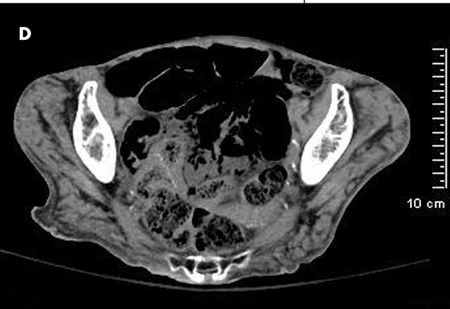

The patient complained of diffuse abdominal pain. She had an erythematous swelling around the right iliac fossa, abdominal guarding, and palpable crepitations. CT scan of the abdomen without contrast showed extensive portal venous air from the small branches in the periphery to the main portal and splenic veins (A and B). Considerable gaseous distention of the small bowel (C and D) and dilated loops of the small bowel were also seen (D and E). These findings were consistent with pneumatosis intestinalis.